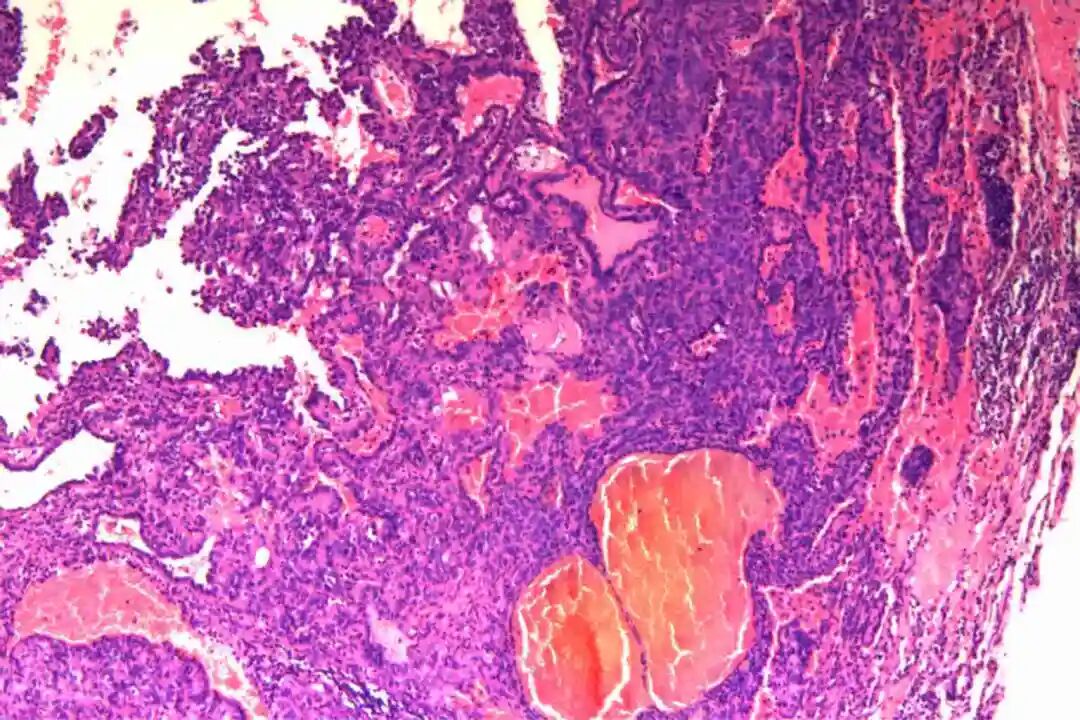

镜下特征:

组织特征:包括硬化区、出血区、实性区和乳头状区四种典型形式。硬化区由大量胶原纤维组成,其间散在分布着间质圆形细胞,这些细胞常围绕血管或呈片状排列。出血区则以红细胞积聚为特征,伴有泡沫状巨噬细胞和含铁血黄素沉积,周围可见表面立方细胞形成的血管样结构。实性区由密集的间质圆形细胞构成,细胞排列成片状或巢状,其间可见少量表面立方细胞覆盖的小管状结构。乳头状区最为复杂,其核心由纤维血管轴组成,表面被覆一层或多层表面立方细胞,周围环绕间质圆形细胞。这四种结构在肿瘤中往往以不同的比例混合存在,形成了PSP独特的病理景观。